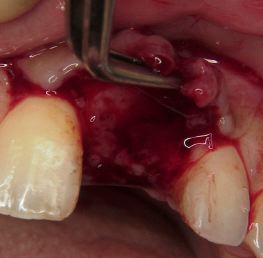

歯茎を開けてみると骨に大きな穴が開いています。

かなり根の病気が悪化していました。

このままではインプラントが打てないため、

この歯を抜くと同時に下顎から骨を採取して

抜いた部分に詰めておきました。

歯茎を開けてみると骨に大きな穴が開いています。

かなり根の病気が悪化していました。

このままではインプラントが打てないため、

この歯を抜くと同時に下顎から骨を採取して

抜いた部分に詰めておきました。